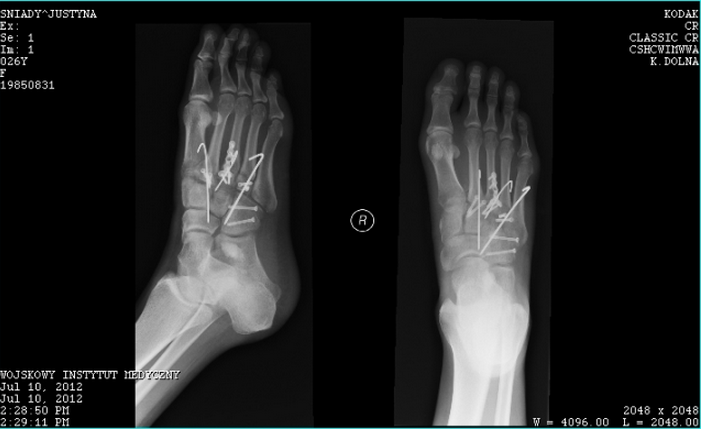

Words by Ellie Ross Justyna Sniady was a promising young windsurfer, competing on the world tour and racking up a series of impressive results. Until she suffered a horrific injury, breaking her foot in several places and requiring multiple surgery, 13 screws and a plate. Doctors then delivered a devastating blow to the 29-year-old athlete. “They told me that I wouldn’t walk again, and that I should forget sport,” she said. “I didn’t want to believe it. The thought of no more windsurfing was the scariest thing ever.” But Justyna, from Warsaw in Poland, has not only climbed back, but has also made it to the top of the podium. This month she was crowned UK Wavesailing Champion and has become the first ever Polish Wavesailing Champion. She is currently second in the world for indoor windsurfing and seventh for wavesailing – and has numerous other trophies under her belt. That fateful day in 2012 however almost put an end to all of this before it had begun. Justyna had arrived three weeks early to train for the Professional Windsurfers Association (PWA) World Tour in Pozo, Gran Canaria. The morning of her second day, she renewed her travel insurance. It would prove to be the wisest decision she made that day. Recalling the accident, Justyna said: “It was my last run out. The wind had really picked up and I could barely hold on to my sail so I was heading in. I went for one more forward loop. It was the move I had been working on – I was doing 50 a day to nail them. “I hit a big ramp and jumped – but I caught a huge gust of wind and wasn’t able to sheet in with my sail. The sail was ripped out of my hands and I fell hard – with my right foot stuck in the footstraps.”

“I thought it had torn half of my foot off. I could feel the pressure of the bone on my skin and I felt sick immediately. I didn’t want to look down because I was scared I would see an open wound with blood and would pass out.” Justyna started shouting and waving for help, but she managed to get herself in from the water by using the power in the sail to ‘body drag’ towards the shore, where she was helped by friends. With her foot swelling up, she had to wait for half an hour for an ambulance to collect her from the beach. But the worst was yet to come. At the local hospital, doctors said they couldn’t give her painkillers until they had seen her passport and insurance – which she didn’t have on her. Still wearing her wetsuit, she waited for two hours before being transferred to a second hospital. It took another five hours before a friend was eventually able to deliver her passport. She said: “They finally gave me a painkiller after seven hours. It was horrendous. My foot was massive. At first I was in shock, but when the pain started kicking in it was pretty bad. And I was gutted about missing the competition – I had trained so hard for it.” Justyna was initially told she would need an operation, but after the results of a CT scan, doctors changed their minds. She said: “I was relieved because I didn’t want screws in my foot. But a friend showed the scan to his dad, who is a surgeon, and told me I was in serious trouble. “He said it looked really bad, like I wouldn’t walk again, and that I needed surgery within two weeks. That’s when I started panicking.” Justyna flew home to Warsaw for surgery, but struggled to find a surgeon willing to carry out the complicated procedure she required. She said: “Private surgeons didn’t want to take the risk, and because I hadn’t come through A&E, I would be on a long waiting list at a public hospital.” But good fortune came in the form of Piotr Piekarczyk, a surgeon at Szaserow Military Hospital. The doctor – whose high-profile patients include the son of Poland’s former president Lech Walesa – regularly reconstructs the limbs of soldiers injured by IEDs and mines. Justyna said: “He saves a lot of people from hardcore injuries. When they want to chop somebody’s leg off, somehow he puts them back together and they walk again. “They held a special conference about my case, and at the end of it he patted me on the head and said he would fix me up. I was incredibly lucky.” Piekarczyk operated on Justyna on the last day of her two-week window, inserting 13 screws and a plate into her foot. The five bones she had broken were so badly shattered that he was forced to embed wires to fuse them back together and to restore the joints. Confined to a wheelchair, Justyna refused to quit the windsurfing world, travelling to Tenerife to work as a commentator for the second leg of the World Tour. “I sat on the beach all day with my foot in the air,” she said. “It beat moping about at home and crying in front of the live stream because I couldn’t be there.” They finally gave me a painkiller after seven hours. After four months, Piekarczyk removed the wires from Justyna’s foot – without anaesthetic.